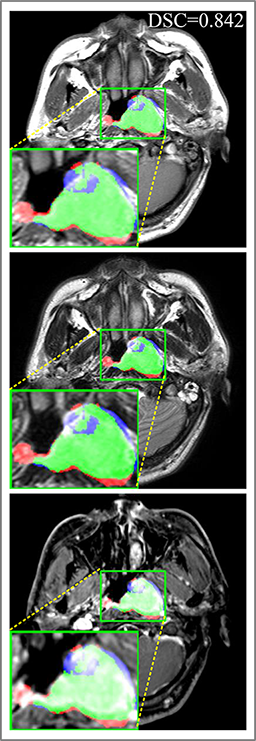

Refer to caption

Figure 9: Predicted results in one single slice image, there are corresponding T1, T2 and CET1 images from top to down. Green regions denote TP𝑇𝑃TP points, red and blue regions denote FP𝐹𝑃FP and FN𝐹𝑁FN point. (a) Ground truth. (b) Patch-based CNN (CET1). (c) Multi-modality patch-based CNN. (d) U-net (CET1). (e) 3D U-net (CET1). (f) Input-level fusion. (g) Merging encoders’ features. (h) MMFNet + multi-MLP + stdPool + self-transfer.

Comparison with related works. Table 1 reports the values of meanDSC𝑚𝑒𝑎𝑛𝐷𝑆𝐶meanDSC, meanASD𝑚𝑒𝑎𝑛𝐴𝑆𝐷meanASD and meanHD𝑚𝑒𝑎𝑛𝐻𝐷meanHD for different methods. Predicted masks of different methods are illustrated in Figure 9 and Figure 10, which respectively present results in 2D and 3D images. Through comprehensively analyzing these results, the proposed MMFNet actually have the following properties:

(i) It directly fuses 3D MRI images rather than 2D slices. Thus, it can effectively use meaningful information from neighboring slices of MRI to realize NPC segmentation. As shown in Table 2, MMFNet can bring 12.26%percent12.2612.26\%, 8.52mm8.52𝑚𝑚8.52mm and 81.19mm81.19𝑚𝑚81.19mm improvements in meanDSC,meanASD𝑚𝑒𝑎𝑛𝐷𝑆𝐶𝑚𝑒𝑎𝑛𝐴𝑆𝐷meanDSC,meanASD and meanHD𝑚𝑒𝑎𝑛𝐻𝐷meanHD compared to the best method based on 2D images (Multi-modality patch-based CNN). And Figure 10 shows that 3D-based methods have less isolated regions (false positives) than 2D-based ones.

(ii) It segments NPC by fusing multi-modality MRIs with the multi-encoder network. Thus, it can learn complementary and interdependent features from different modalities of MRI for final decisions. Additionally, comparing with input-level fusion networks and decision-level fusion networks, layer-level fusion networks (including MMFNet) can effectively capture informative features from different modalities of MRI and fuse low-level features and high-level features.

(iii) It uses a fusion block to fuse low-level features from different modalities of MRI and prepare these low-level features for the fusion with high-level features. Thus, it can more effectively fuse information from various sources. It also uses the self-transfer strategy to initialize the netwerk. Hereby, it can stimulate encoders to make full mining of meaningful features from modality-specific MRI. And it finally improve base multi-encoder-based network (Merging encoders’ fetures) by 2.64%percent2.642.64\%, 1.10mm1.10𝑚𝑚1.10mm and 11.88mm11.88𝑚𝑚11.88mm in meanDSC,meanASD𝑚𝑒𝑎𝑛𝐷𝑆𝐶𝑚𝑒𝑎𝑛𝐴𝑆𝐷meanDSC,meanASD and meanHD𝑚𝑒𝑎𝑛𝐻𝐷meanHD.